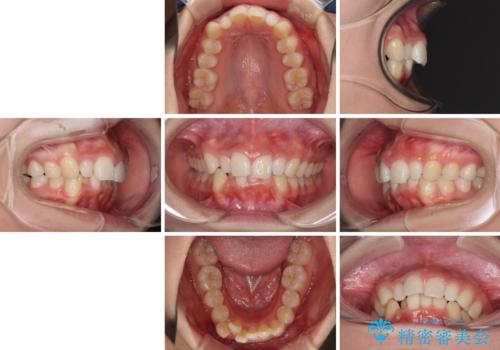

- 前歯のデコボコ気になるとのことで来院された患者様です。

上下顎ともに歯列全体の後方移動とIPR(歯と歯の間を削る)によってデコボコが解消するように設計し、インビザラインにより治療を行うこととしました。

上顎左右前歯に矮小歯があるため、上顎の奥歯は下顎に対して相対的に前方に位置することになりました。

それでも奥歯の咬みにくさはなく、患者様には大変満足していただきました。